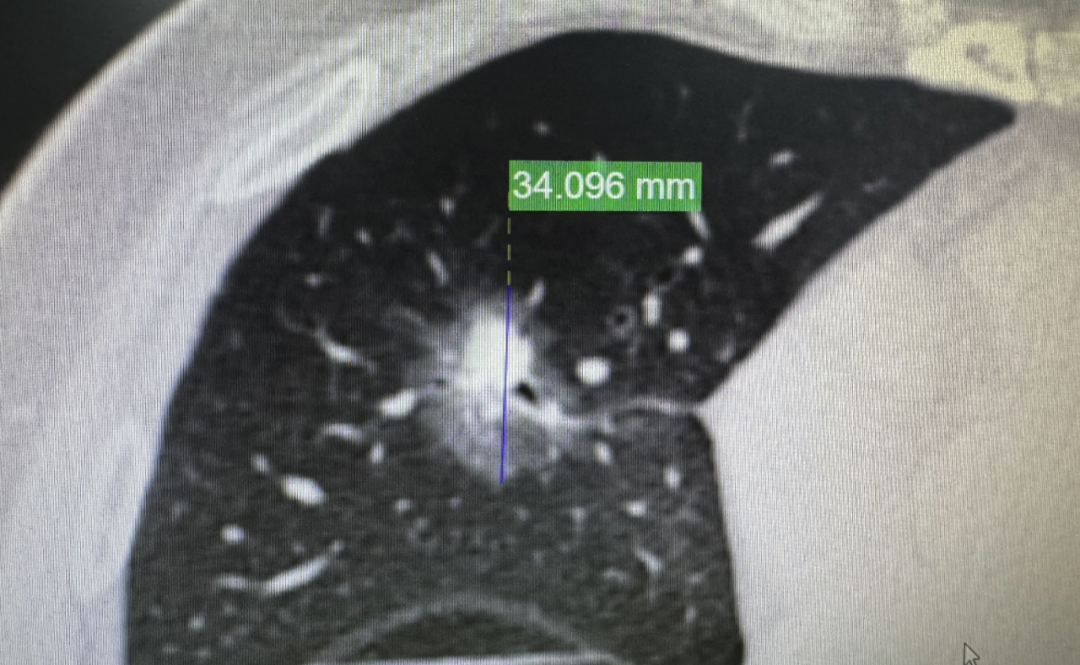

2016年6月,张先生在体检中发现了右肺中叶一个混合磨玻璃结节。

直径约34mm,也就是3.4公分。密度不均匀,里面的实性成分大约16mm,CTR(实性占比)约50%。

CT影像

这种形态的结节,在影像学上一看就是恶性肿瘤,而且不可能是原位癌或微浸润——至少是浸润性腺癌。